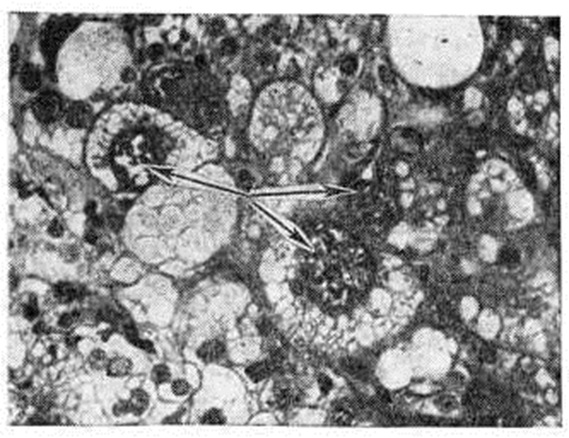

Злокачественная Гибернома выделена из группы липосарком (смотри), отличается от них более длительным течением, реже метастазирует. Локализация её, возраст и пол больных те же, что и при доброкачественных Гибернома Опухоль дольчатого вида буроватого цвета, нередко с изъязвлением и очагами некроза. Микроскопически отмечается выраженный полиморфизм клеток (рисунок 2), характерны гигантские многоядерные клетки, содержащие в цитоплазме мелкокапельный жир (уродливые «тутовые» клетки). Нередко встречаются участки, напоминающие липосаркому, полиморфноклеточную саркому, рабдомиобластому. Злокачественные Гибернома следует дифференцировать с липосаркомой, метастазом гипернефроидного рака, рабдомиосаркомой.

Рисунок 2. | ||